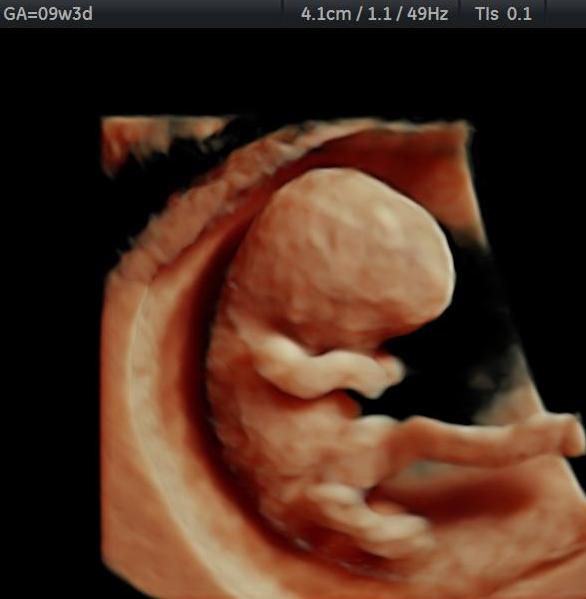

Φωτογραφίες από το αρχείο και από το χώρο του ιατρείου του γυναικολόγου Βυθούλκα Κωνσταντίνου, καθώς και του εργαστηρίου της κυτταρολόγου Λιβέρη Κατερίνας.